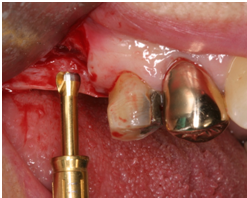

2) 以不翻瓣,無傷害的方式移除牙齒: 先以15c刀片切開supracrestal fiber, 必要時切割牙齒 (fig 8,9)

4) 將植體依正確位置放入; 植體位置需稍偏palatal且植體的頂部需稍低於頰側骨嵴 (在free gingival margin下3-4mm) , 植體的咬面觀離頰側骨壁約有2mm 的空隙 (fig 10,11)